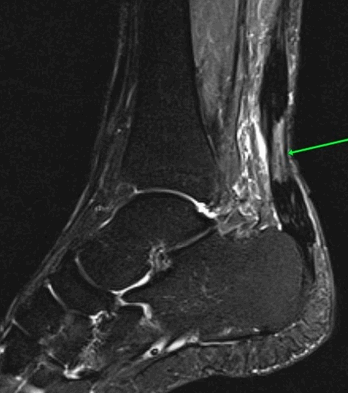

На Т2-ВИ в сагиттальной и корональной плоскостях определяется стресс-перелом дистальных отделов малоберцовой кости.